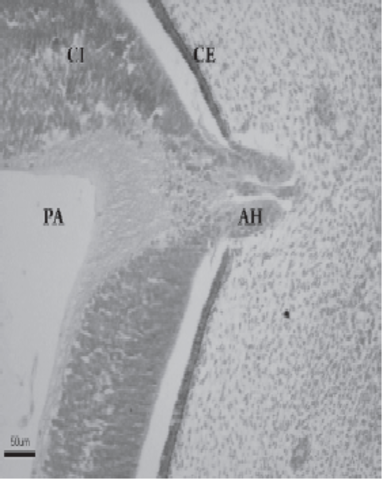

El iris se forma a partir del reborde de la cúpula óptica,

cubriendo parcialmente al cristalino. El epitelio iridiano

presenta las dos capas de la cúpula óptica; se continúa con el epitelio del cuerpo ciliar y con el epitelioretiniano pigmentario y sensorial.